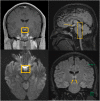

Observations: We report the case of a 36 year old with a post-COVID episode of acute-subacute onset bilateral blindness ultimately diagnosed as Wernicke's syndrome based on MRI findings and clinical response to high dose IV thiamine supplementation.